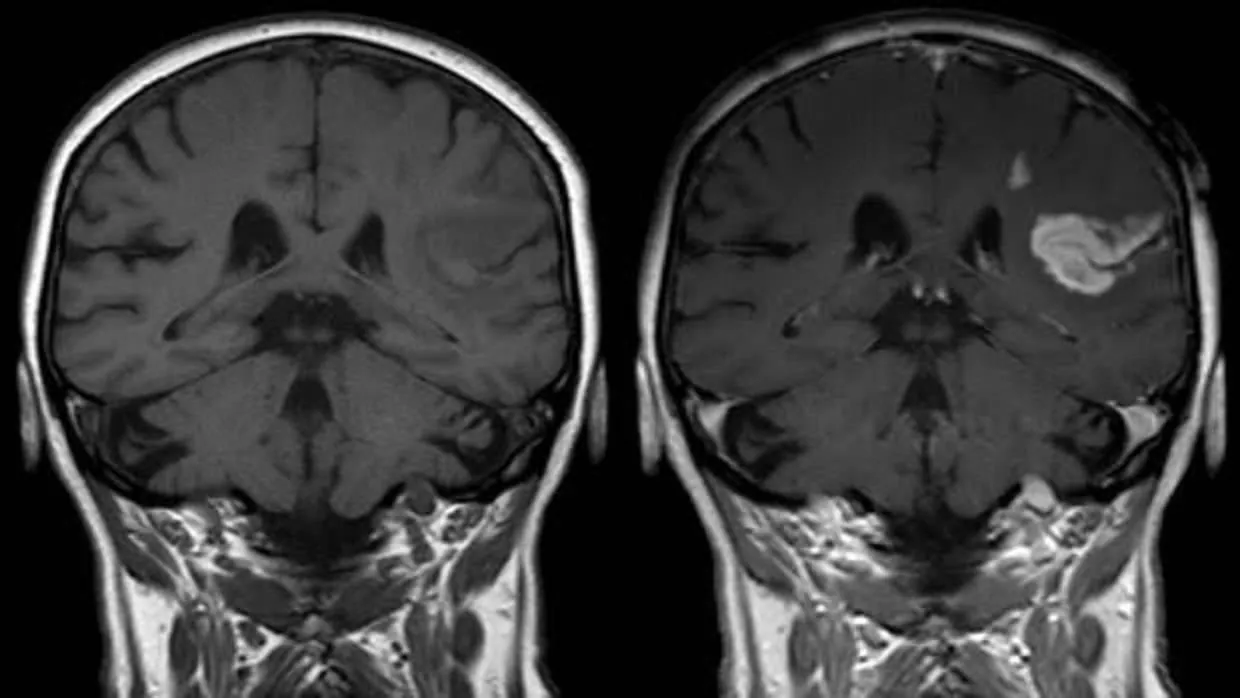

Como explica Hiroki Abe, director de esta investigación publicada en la revista « Science », «tras un accidente cerebrovascular que ha provocado un daño cerebral, las neuronas pueden establecer nuevas conexiones de forma natural. Un proceso adaptativo denominado ‘plasticidad’ que permite a los afectados recuperar algunas funciones como la movilidad o el habla. Sin embargo, y si bien mediante la rehabilitación se pueden crear nuevas conexiones cerebrales hasta cierto punto, aún no se ha aprobado ningún fármaco que mejore la plasticidad cerebral y facilite la recuperación tras un ictus ».

Distintos estudios han constatado la existencia en el sistema nervioso de una proteína que, denominada ‘proteína mediadora de respuesta a colapsina 2’ (CRMP2), juega un papel muy importante en la plasticidad cerebral y el aprendizaje. Por ello, el objetivo del estudio fue evaluar si la administración de un fármaco experimental que, bautizado como ‘T-817’, se une específicamente a la CRMP2, podría mejorar la plasticidad cerebral y, por ende, mejorar la recuperación de las funciones motoras tras un ictus. Y para ello, los autores recurrieron a sendos modelos animales –ratones y monos.